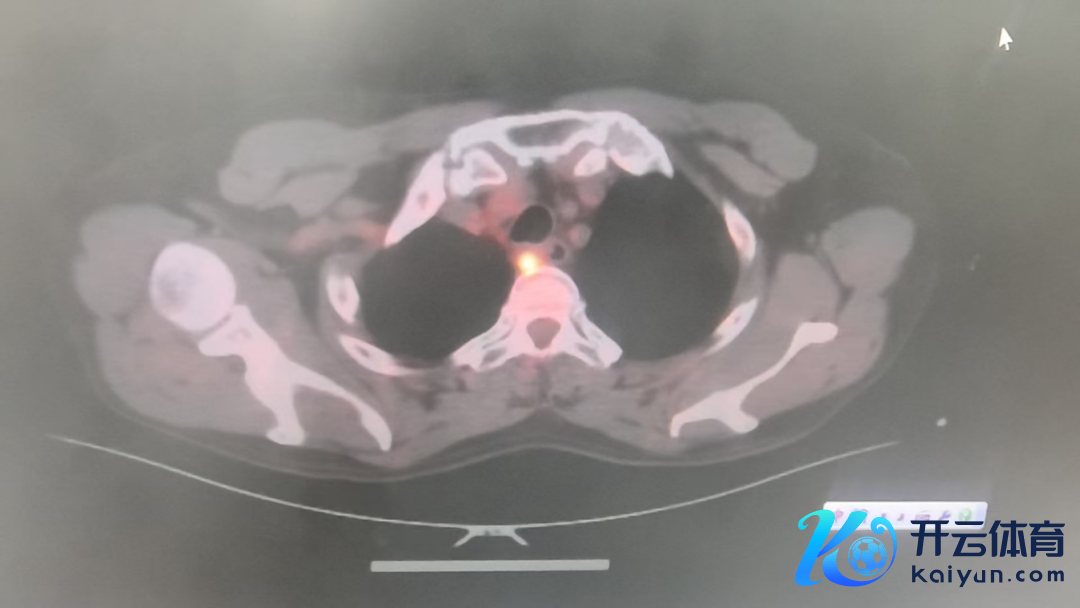

心怀外科副主任、主任医师王理智,主治医师刘炬博士团队接到诊断后,为陈阿公进行全面查验。胃镜领导:肿瘤位于食管启齿处,厚11mm,冲破食管外层,仍是环绕食管3/4周,周围多发肿大淋献媚;CT领导:食管高位肿瘤,48mm*18mm*16mm,与支气管后壁分界不清,周围多发淋献媚;PET-CT领导:2-4胸椎水平食管上段食管癌,右下颈气管旁、右上气管旁淋献媚疑退换。抽象计划局部晚期、高位、食管恶性肿瘤,径直进行手术的风险及难度齐很大,大夫提倡实验新扶助调养后再进行手术。但这样的调养形状,让家属们堕入两难境地。

△查验效能